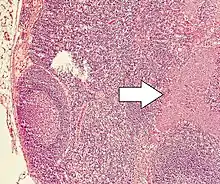

| Micrograph of a neuroendocrine tumor. H&E stain. | |

NETs are often small, yellow or tan masses, often located in the submucosa or more deeply intramurally, and they can be very firm due to an accompanying intense desmoplastic reaction. The overlying mucosa may be either intact or ulcerated. Some GEP-NETs invade deeply to involve the mesentery.[72] Histologically, NETs are an example of "small blue cell tumors," showing uniform cells which have a round to oval stippled nucleus and scant, pink granular cytoplasm. The cells may align variously in islands, glands or sheets. High power examination shows bland cytopathology. Electron microscopy can identify secretory granules. There is usually minimal pleomorphism but less commonly there can be anaplasia, mitotic activity, and necrosis.